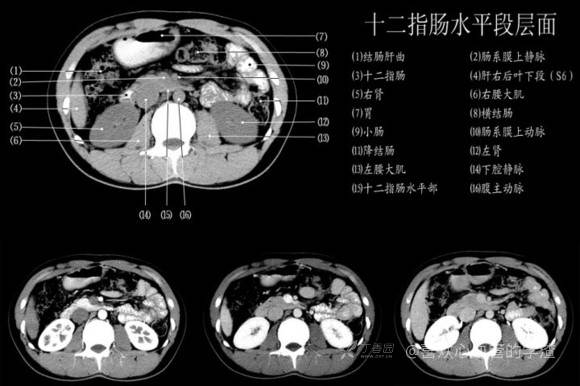

其实你离掌握上腹部 CT 影像只有一套高清实用图谱的距离,下面把我最喜欢的这本图谱分享给大家,为了方便阅读,我加了中文标识。后面附赠几张血管相对位置解剖关系图片,帮助大家理解(文中多图,建议在 wifi 环境下查看)。